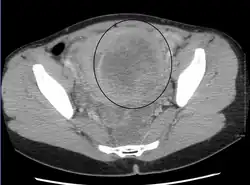

A relatively large submucosal leiomyoma; it fills out the major part of the endometrial cavity.

-